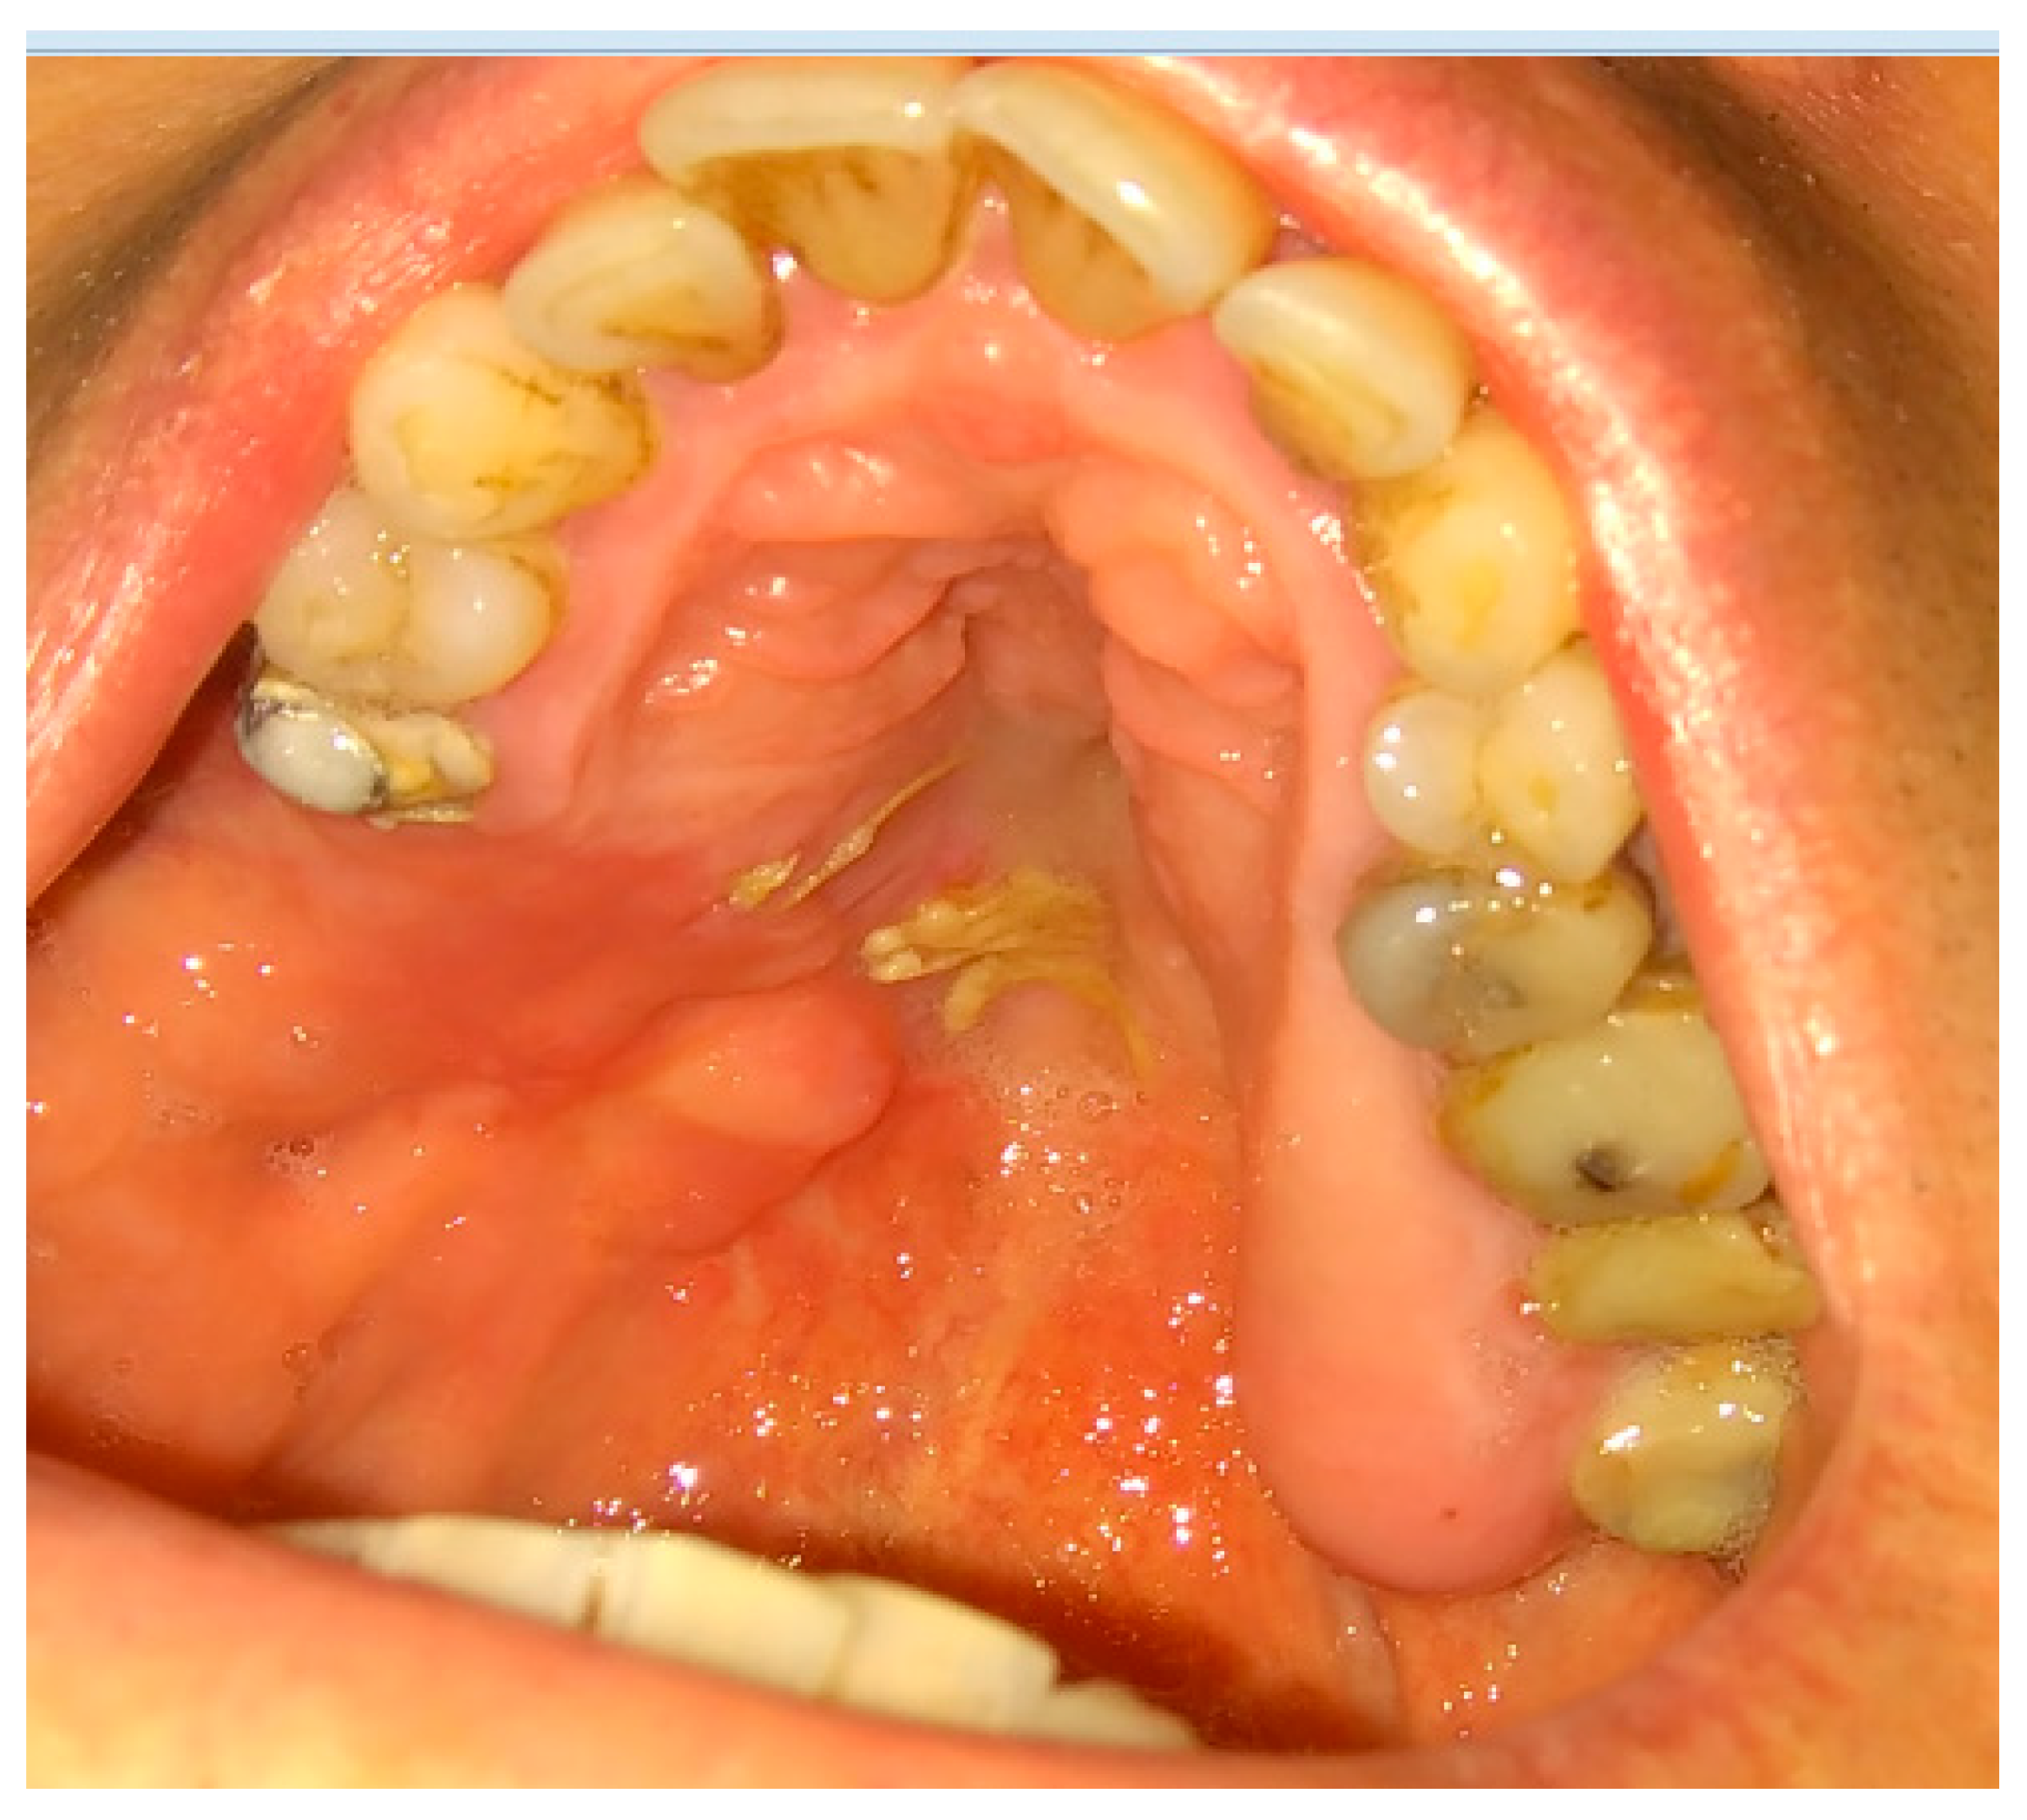

Figure 4. A very good result with limited buccal corridor narrowing and good tissue volume at the top of the dental arch.